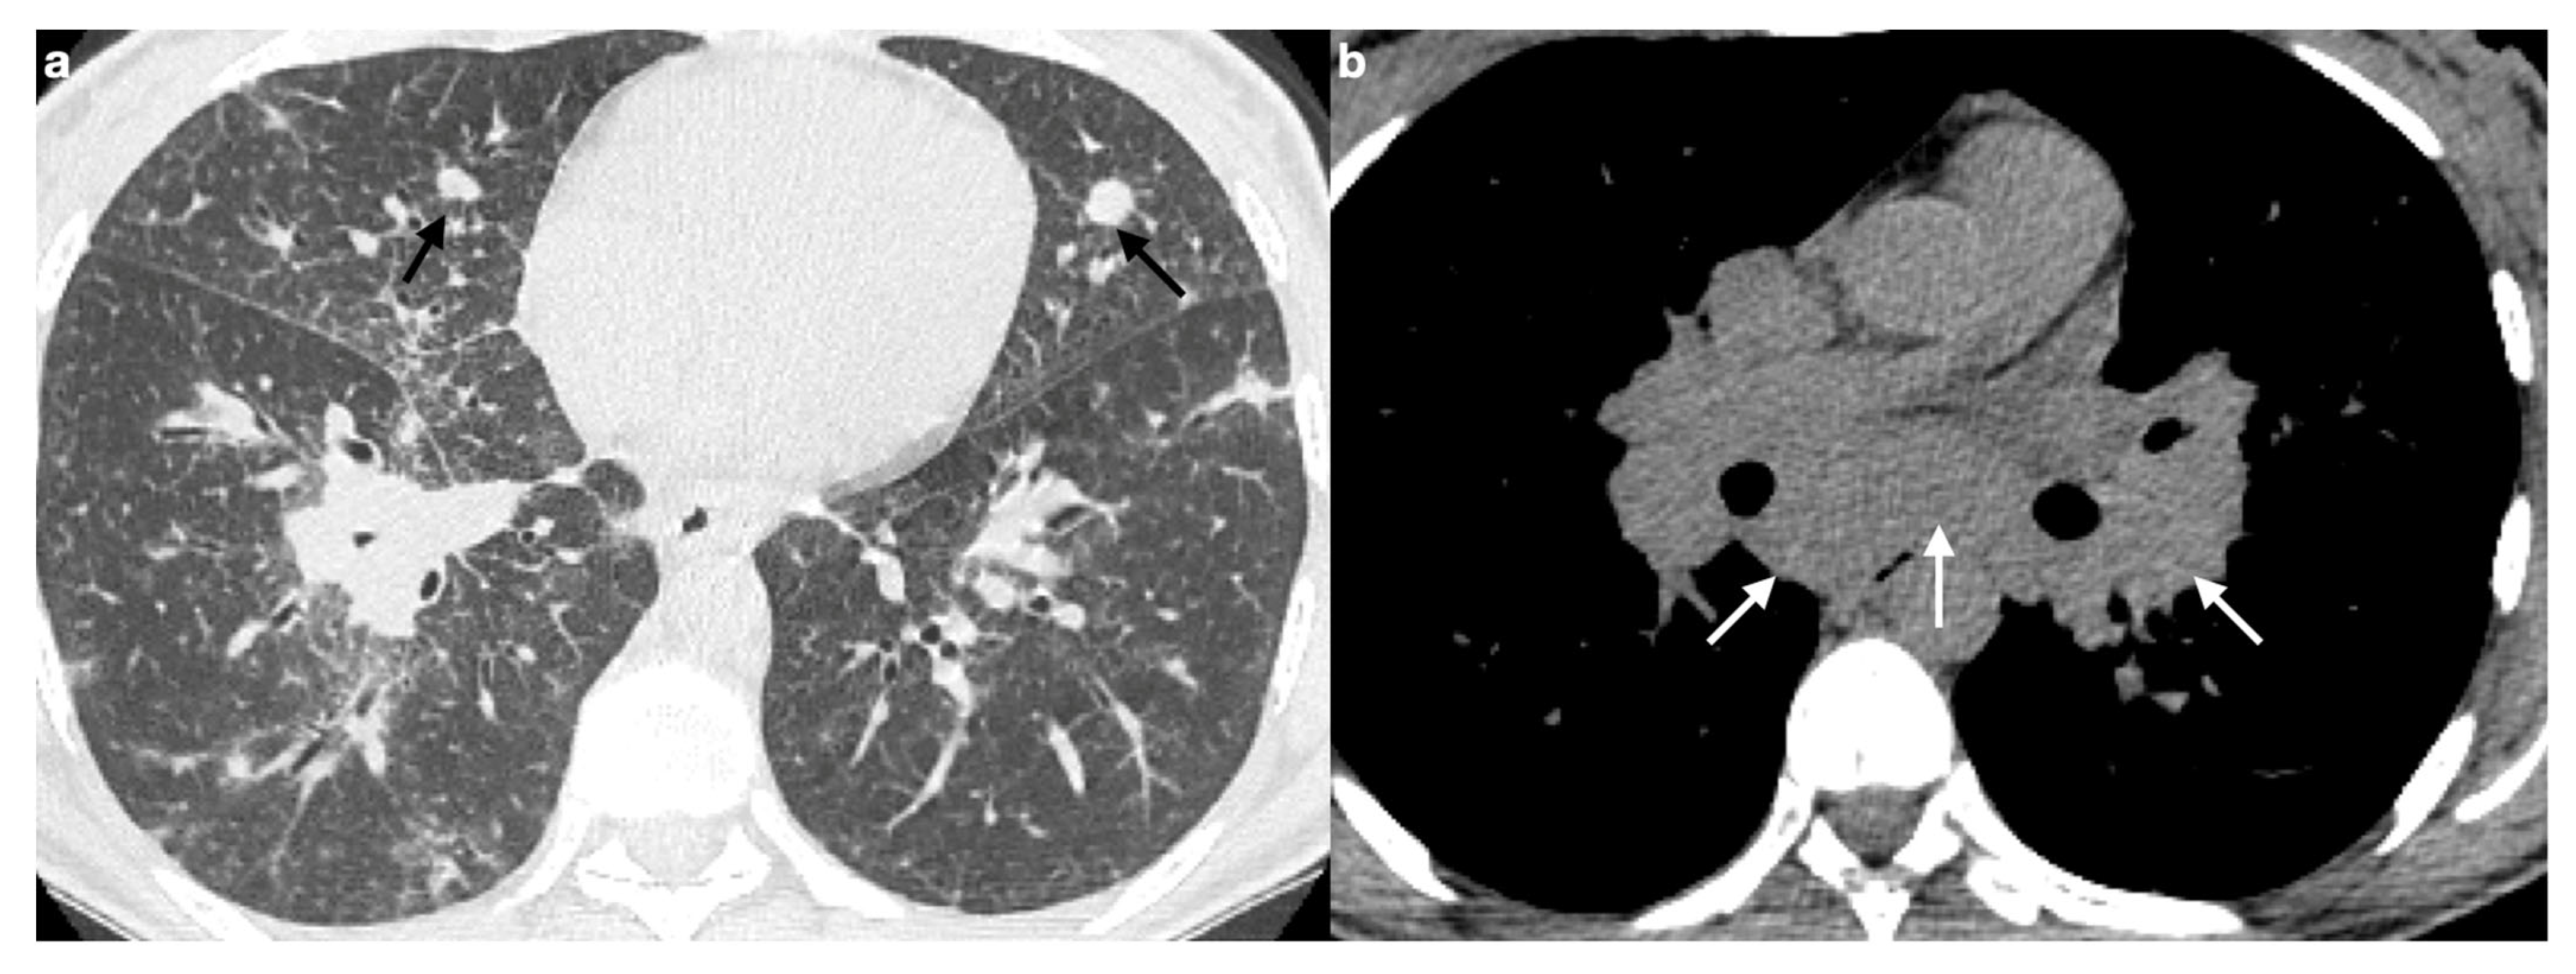

3. Lymphadenopathy

3.1. Typical Imaging

Calcifications

3.2. Atypical Imaging